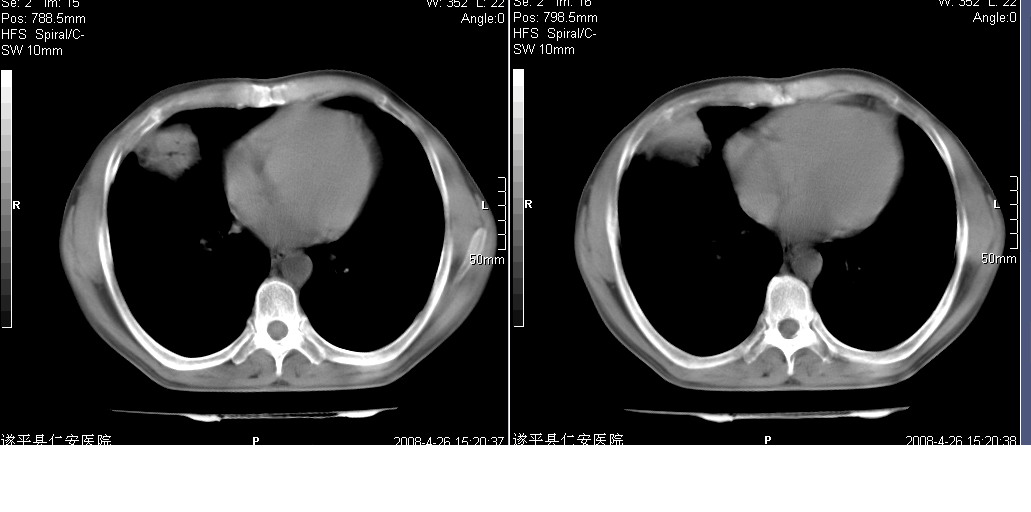

以下是引用yangyudong333在2008-4-27 16:58:00的发言:[br]病灶无明显分叶,周围有粗大索条影,外侧与胸膜接触面较宽且胸膜下透亮层存在,内部可见充气支气管,考虑炎症可能性大,建议抗炎治疗后复查

以下是引用mzh123在2008-4-27 19:30:00的发言:[br]右肺中叶团片致密影,周围可见卫星病灶,中叶支气管未见明显狭窄,所以首先考虑炎性病变,结核可能性大,肺癌待排,请治疗后复查!

以下是引用随光逐影在2008-4-27 20:49:00的发言:[br]考虑为:1)右肺中叶及左侧下叶感染性病变。2)左肺下叶支气管扩张?建议:抗炎治疗后复查。